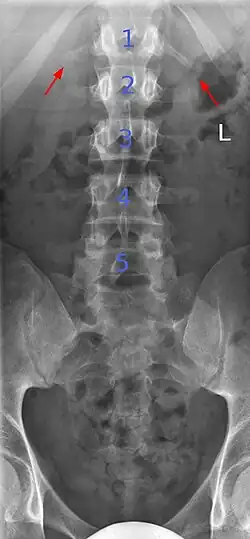

Ein Übergangswirbel (Syn.: Assimilationswirbel, Schaltwirbel[1]; engl. transitional vertebra, assimilated vertebra) ist eine angeborene Variation an den Grenzen der Wirbelsäulenabschnitte, die sich bei bis zu 35 % der Bevölkerung findet.[2] Übergangswirbel haben die Formen und Eigenschaften der angrenzenden Wirbelregionen ganz oder teilweise angenommen.

Typische Beispiele sind die Sakralisation des 5. Lendenwirbels (Lumbalwirbels) – in diesem Fall ist der 5. Lendenwirbelkörper mit dem ersten Kreuzbeinwirbelkörper ohne funktionelle Bandscheibe knöchern verwachsen – oder die Lumbalisation des 1. Kreuzwirbels, hier gibt es eine Bandscheibe zwischen dem ersten und zweiten Kreuzwirbel, so dass der erste Kreuzwirbel funktionell als zusätzlicher (sechster) Lendenwirbel anzusehen ist.

Unterschieden werden vollständige und partielle (teilweise) Übergangswirbel, je nach Stärke der Assimilation. Bei den partiellen Übergangswirbeln kommen auch Formen vor, bei denen eine Seite assimiliert ist, während die andere Seite unverändert ist, was dann zu asymmetrischen Bewegungsmustern dieses Wirbelsäulenabschnitts führen kann.

Diese häufigste Übergangsstörung kann nach Castellvi je nach der Form der Querfortsätze und deren Verbindung zum Kreuzbein in vier Ausprägungen klassifiziert werden, wobei mit höherem Ausprägungsgrad eine stärkere Sakralisation und mit niedrigerem Ausprägungsgrad eine stärkere Lumbalisation des Übergangswirbels verbunden ist, dies aber keine Korrelation zu eventuellen Beschwerden hat. Die Grade 1–3 werden zudem unterteilt, je nachdem, ob der Befund einseitig (A) oder beidseitig (B) vorliegt:[4]

- Der Querfortsatz ist einseitig (1A) oder beidseitig (1B) vergrößert und verbreitert, ohne gelenkige oder knöcherne Verbindung zum Kreuzbein

- Der Querfortsatz ist einseitig (2A) oder beidseitig (2B) vergrößert und hat eine gelenkige Verbindung zum Kreuzbein

- Der Querfortsatz ist einseitig (3A) oder beidseitig (3B) vergrößert und über eine Knochenverbindung mit dem Kreuzbein fusioniert

- Beide Querfortsätze sind vergrößert, einer ist knöchern mit dem Kreuzbein verbunden und der andere gelenkig.